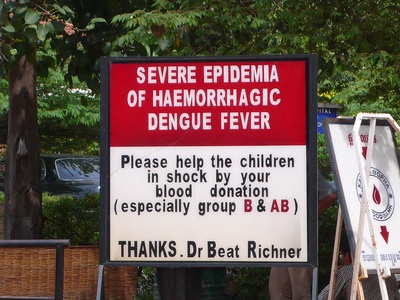

Dengue fever

Dengue causes high fever, severe joint and muscle pain and sometimes hemorrhagic complications. Transmitted by Aedes mosquitoes in tropical and subtropical areas. Vaccination exists but is limited to certain populations and prior infection status; mosquito control and bite prevention reduce risk.